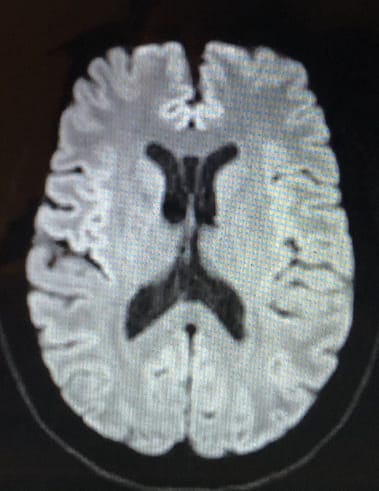

I like to view my MRI and CT scan images, even though I can’t interpret them fully. The images are like little snapshot slices of your brain, creating a point in time view of the current state. But, at certain points, you get a different view. While building up to what my ventricles look like, the image above formed, and it looked like a grumpy face to me. (Hence the title of this post),